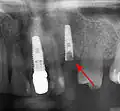

Установка зубных имплантатов может вести к периимплантиту, который возникает из-за бактериальной флоры, попадающей на внешнюю поверхность имплантатов через зубной налет. Лечение данного заболевания проводили корейские исследователи с использованием титановой щетки.

- с помощью рентгенографии изучаются качество и плотность костной ткани;